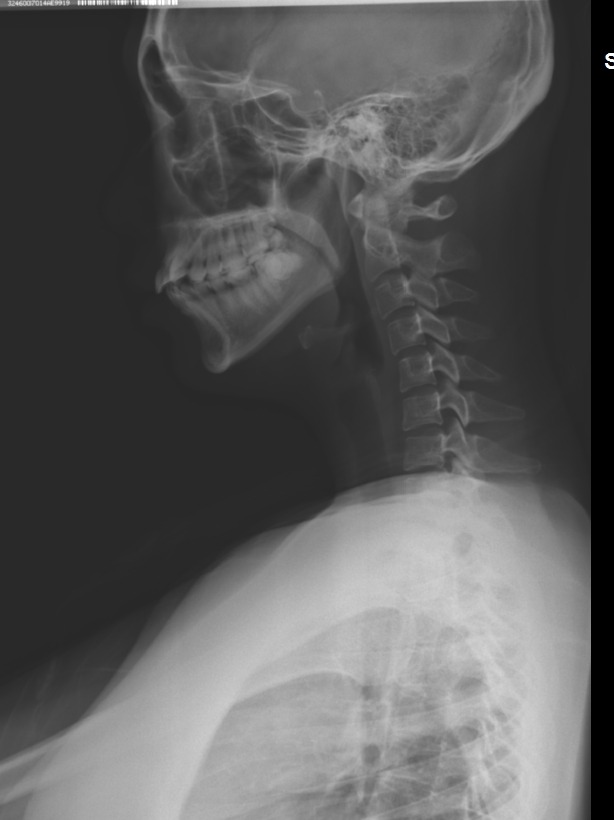

5. 경추 reverse curve

- 거의 모든 측만증에서 경추는 일자목 or reverse curve임.